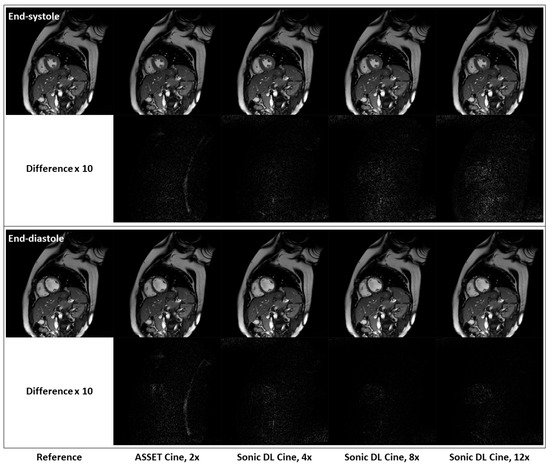

Figure 5 shows fully sampled and retrospectively under-sampled cine images from a healthy volunteer in the short-axis plane. At both end-systole and end-diastole phases, Sonic DL Cine-reconstructed images exhibit comparable SNR, contrast, and sharpness to both ASSET (acceleration factor = 2) and fully sampled cine images. Difference maps between the under-sampled and fully sampled images also confirm that Sonic DL Cine can reconstruct high-quality cine images from highly under-sampled k-space data with minor discrepancies from the fully sampled reference images. The difference between the under-sampled and fully sampled images is more visible when high acceleration (e.g., 12-fold acceleration) is applied. Additionally, retrospectively under-sampled and fully sampled cine images acquired on two-chamber, three-chamber, and four-chamber planes from representative subjects are shown in Figure 6. From all these different planes, Sonic DL Cine images closely match ASSET (acceleration factor = 2) and fully sampled cine images in terms of SNR, sharpness, and contrast, which is also demonstrated by difference maps between under-sampled and fully sampled images. Increased acceleration factors make the difference between Sonic DL Cine and fully sampled reference images more visible.

Figure 6.

Representative fully sampled and retrospectively under-sampled cine images from the two-chamber, three-chamber, and four-chamber planes. Fully sampled and retrospectively under-sampled cine images with ASSET (acceleration factor = 2), and Sonic DL Cine (acceleration factors = 4, 8, and 12) on the two-chamber, three-chamber, and four-chamber planes are shown from top to bottom. Difference maps, amplified by a factor of 10, between the under-sampled and fully sampled cine images are also calculated.